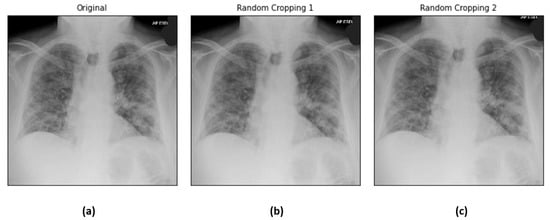

The dataset is challenging as it is highly imbalanced with 184 COVID-19 images and 5000 non-COVID-19 images. Not only that, the signs in the lungs that indicate the infection by the SARS-CoV-2 virus are hardly perceivable and diversified. Some sample COVID-19 and non-COVID-19 images are shown in Figure 1. In light of this, conventional machine-learning methods that require manual feature engineering to describe the images are ineffective. Therefore, the deep neural networks that are able to autonomously learn the prominent features and perform recognition are preferred in this COVID-19 diagnosis task.

Figure 1. Some sample COVID-19 and non-COVID-19 images from the COVID-Xray-5k dataset.